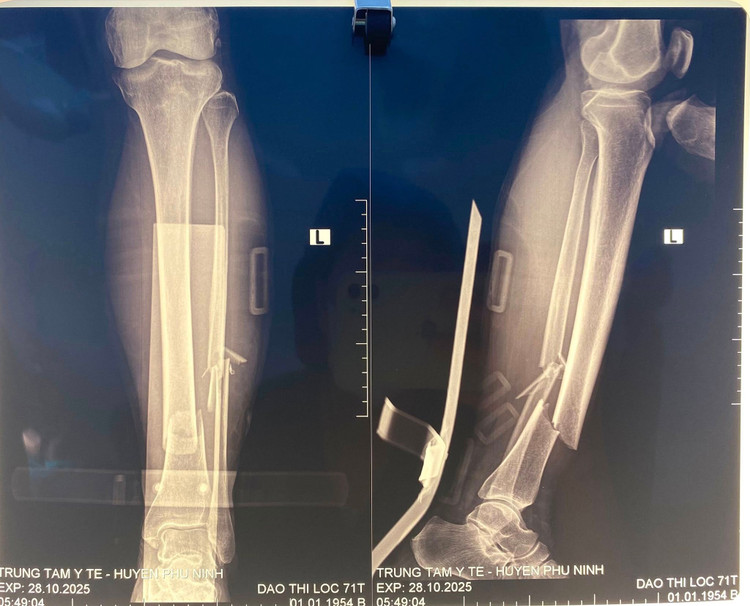

Khi nhập viện, người bệnh trong tình trạng đau nhiều, sưng nề, biến dạng vùng cẳng chân trái, không thể cử động được. Sau khi thăm khám, chụp X-quang và hội chẩn, các bác sĩ chẩn đoán gãy kín hai xương cẳng chân trái di lệch, có chỉ định phẫu thuật kết hợp xương bằng nẹp vít nhằm phục hồi chức năng vận động cho người bệnh.

gay-xuong-2.jpg

Hình ảnh xương gãy trên phim chụp - Ảnh BVCC